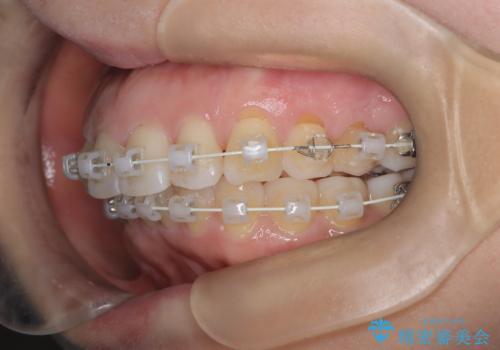

審美装置を用いたワイヤー矯正|非抜歯で歯の凸凹を改善

- 患者様は**歯の凸凹(叢生)**を気にされて来院されました。診査の結果、歯列のスペースが不足しているものの、抜歯をせずに改善できる状態でした。そこで、目立ちにくい審美装置(白いブラケットとホワイトワイヤー)を使用したワイヤー矯正を提案しました。歯列のアーチを広げながら、適宜IPR(歯の幅をわずかに調整する処置)を行い、非抜歯で自然な歯並びへと導く計画を立てました。

治療では、白いブラケットとホワイトワイヤーを使用し、矯正装置が目立ちにくいよう配慮しました。歯列を拡大しながら適切に歯を移動させ、IPRを併用することで、無理なくスペースを確保しました。見た目に配慮しながら、歯の凸凹をスムーズに整え、噛み合わせも改善。患者様からは「装置が思ったより目立たず、歯並びがきれいになって嬉しい」との声をいただきました。